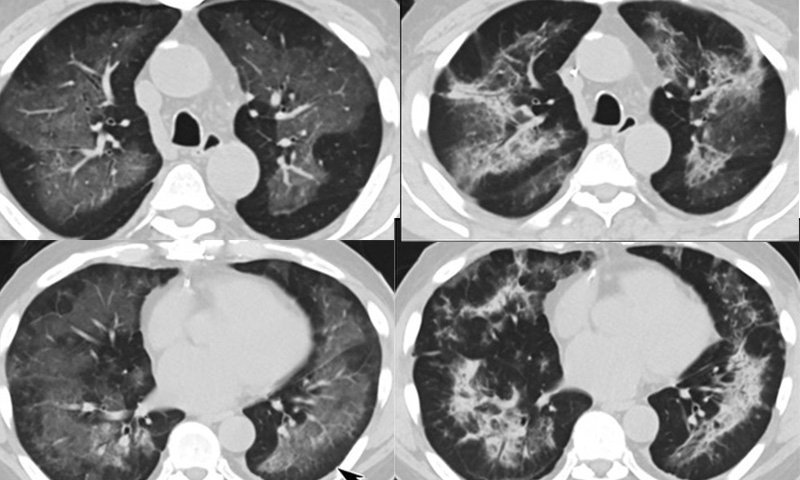

Evali вирус 100 фото